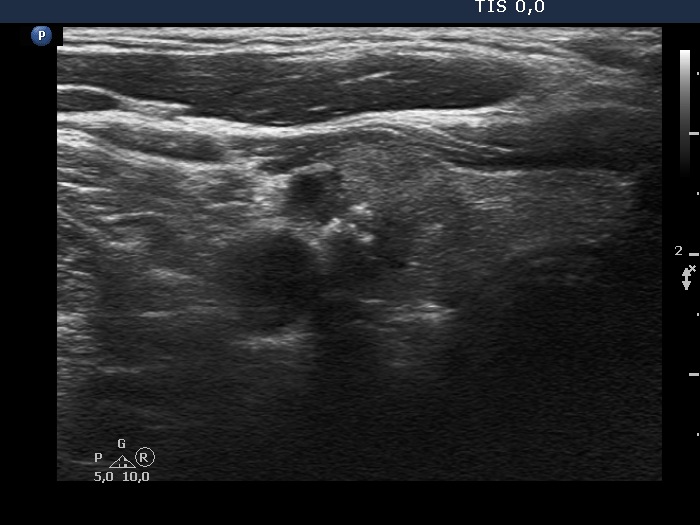

Ultrasonography. The thyroid was echonormal. There was a moderately hypoechoic nodule in the lower part of the right lobe. The lesion presented irregular borders and microcalcifications.